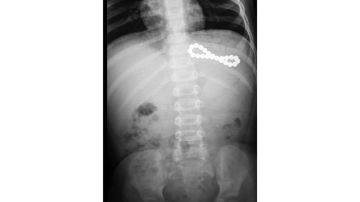

وبيّن أن التعامل الطبي مع هذه الحالات يعتمد على عدد الكرات ومكانها ووقت ابتلاعها، حيث يتم التقييم الفوري باستخدام الأشعة السينية لتحديد العدد والموقع. وفي حال ابتلاع كرة واحدة فقط، قد تتم المراقبة الدقيقة في ظروف محددة، أما عند ابتلاع أكثر من كرة، فلا يُنصح بالانتظار في معظم الحالات، فإذا كانت الكرات في المعدة، قد يتم استخراجها بالمنظار بشكل عاجل، أما إذا تجاوزت المعدة أو ظهرت علامات خطر، تصبح الجراحة الفورية ضرورة لا تحتمل التأجيل.

وأوضح أن نتائج الدراسة كشفت عن مؤشرات مقلقة، حيث تم تسجيل 114 حالة ابتلاع كرات مغناطيسية بين الأطفال خلال فترة البحث، لافتاً إلى أن من أخطر هذه الحالات طفلة تبلغ من العمر تسع سنوات في دبي ابتلعت 28 كرة مغناطيسية، إضافة إلى حالة أخرى لطفلة ابتلعت 26 كرة مغناطيسية.

وأشار إلى أن الدراسة وثّقت حالات استدعت تدخلات جراحية معقدة لإزالة سلاسل مغناطيسية أو علاج مضاعفاتها الخطيرة، مثل تكوّن نواسير بين المعدة والأمعاء، أو بين أجزاء الأمعاء نفسها، فضلاً عن تسجيل حالة نادرة لتكوّن ناسور بين المريء والقصبة الهوائية، ما استدعى استئصال الجزء المصاب جراحياً.